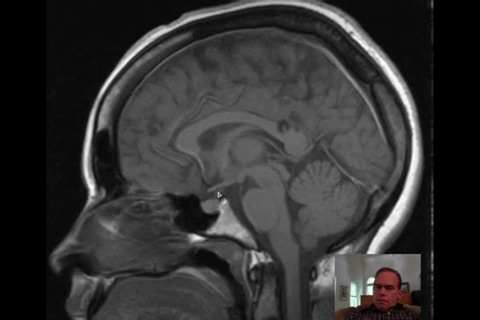

随着科技日新月异,新型医疗仪器不断推陈出新,让医疗专业人员在疾病诊断上,提供极大的帮助。除往日的X光,计算机X射线断层造影术(Computed Tomography, CT),B超(Ultrasound)外,新型的工具包括磁共振显像(MRI),核医学(Nuclear Medicine, NM),如正电子发射断层照相术(Positron Emission Tomography, PET),单光子发射体层摄影术(Single-Photon Emission Tomography, SPET) 等等。新型的工具能减少对病人的伤害和提供不同方面的诊断资讯。

有见及此,我们制作了本程式,以来自海外的英语放射诊断科视频, 提供各种诊断个案,并加以评述,望能帮助医生,作出更符合临床表现的诊断,是医生和医学院校的学生学习影像诊断入门的必备软件。